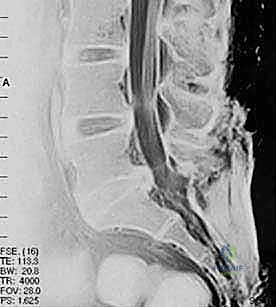

لفهم كيفية عمل تقنيات PLIF و TLIF، يجب أولاً فهم تشريح العمود الفقري القطني. يتكون الجزء السفلي من الظهر من خمس فقرات قطنية (L1 إلى L5). بين كل فقرة وأخرى يوجد "قرص غضروفي" (Disc) يعمل كوسادة لامتصاص الصدمات وتسهيل الحركة. يمر الحبل الشوكي والأعصاب الشوكية عبر قناة عظمية تُسمى "القناة الشوكية".

عندما تتآكل هذه الأقراص الغضروفية بسبب التقدم في العمر أو الإصابات، أو عندما تتحرك الفقرات من مكانها الطبيعي، يحدث تضيق في القناة الشوكية أو ضغط مباشر على جذور الأعصاب. هذا الضغط الميكانيكي هو المسبب الرئيسي للألم المبرح الذي يمتد غالبًا إلى الساقين (ما يُعرف بعرق النسا).

- الانزلاق الفقري (Spondylolisthesis): انزلاق فقرة فوق الفقرة التي تحتها، مما يسبب عدم استقرار ميكانيكي وضغطاً عصبياً.

في هذه التقنية، يتم الوصول إلى العمود الفقري من الخلف مباشرة. يقوم الجراح بإزالة جزء من العظم (الصفيحة الفقرية Laminectomy) للوصول إلى القناة الشوكية. يتم سحب الأعصاب برفق إلى الجانبين للوصول إلى القرص التالف وإزالته، ثم يتم إدخال "أقفاص" (Cages) مدعومة بطعوم عظمية من كلا الجانبين.

الخطوة 2: إزالة الضغط العصبي (Decompression)

يقوم د. هطيف بإزالة الأجزاء العظمية الضاغطة (Laminectomy أو Facetectomy) والأربطة المتضخمة بدقة ميكروسكوبية لتحرير الأعصاب الشوكية المختنقة.

الخطوة 3: استئصال القرص التالف (Discectomy)

يتم تفريغ القرص الغضروفي التالف بالكامل، وإعداد المساحة بين الفقرتين (Endplates) لاستقبال الطعم العظمي. هذه الخطوة حاسمة لضمان التحام العظام لاحقاً.